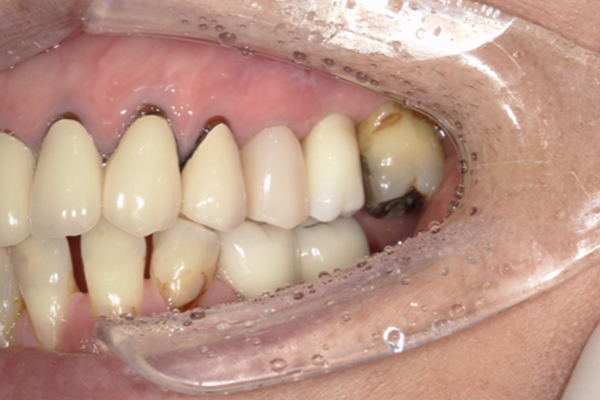

| 主訴 | 歯がグラグラして噛めない |

|---|---|

| 治療内容 | 上顎に対するインプラント治療 |

| 治療期間 | 1日 |

| 治療費 | 204万6千円 |

| 治療 リスク | 最終的な歯が入るまでは仮歯になります。 |